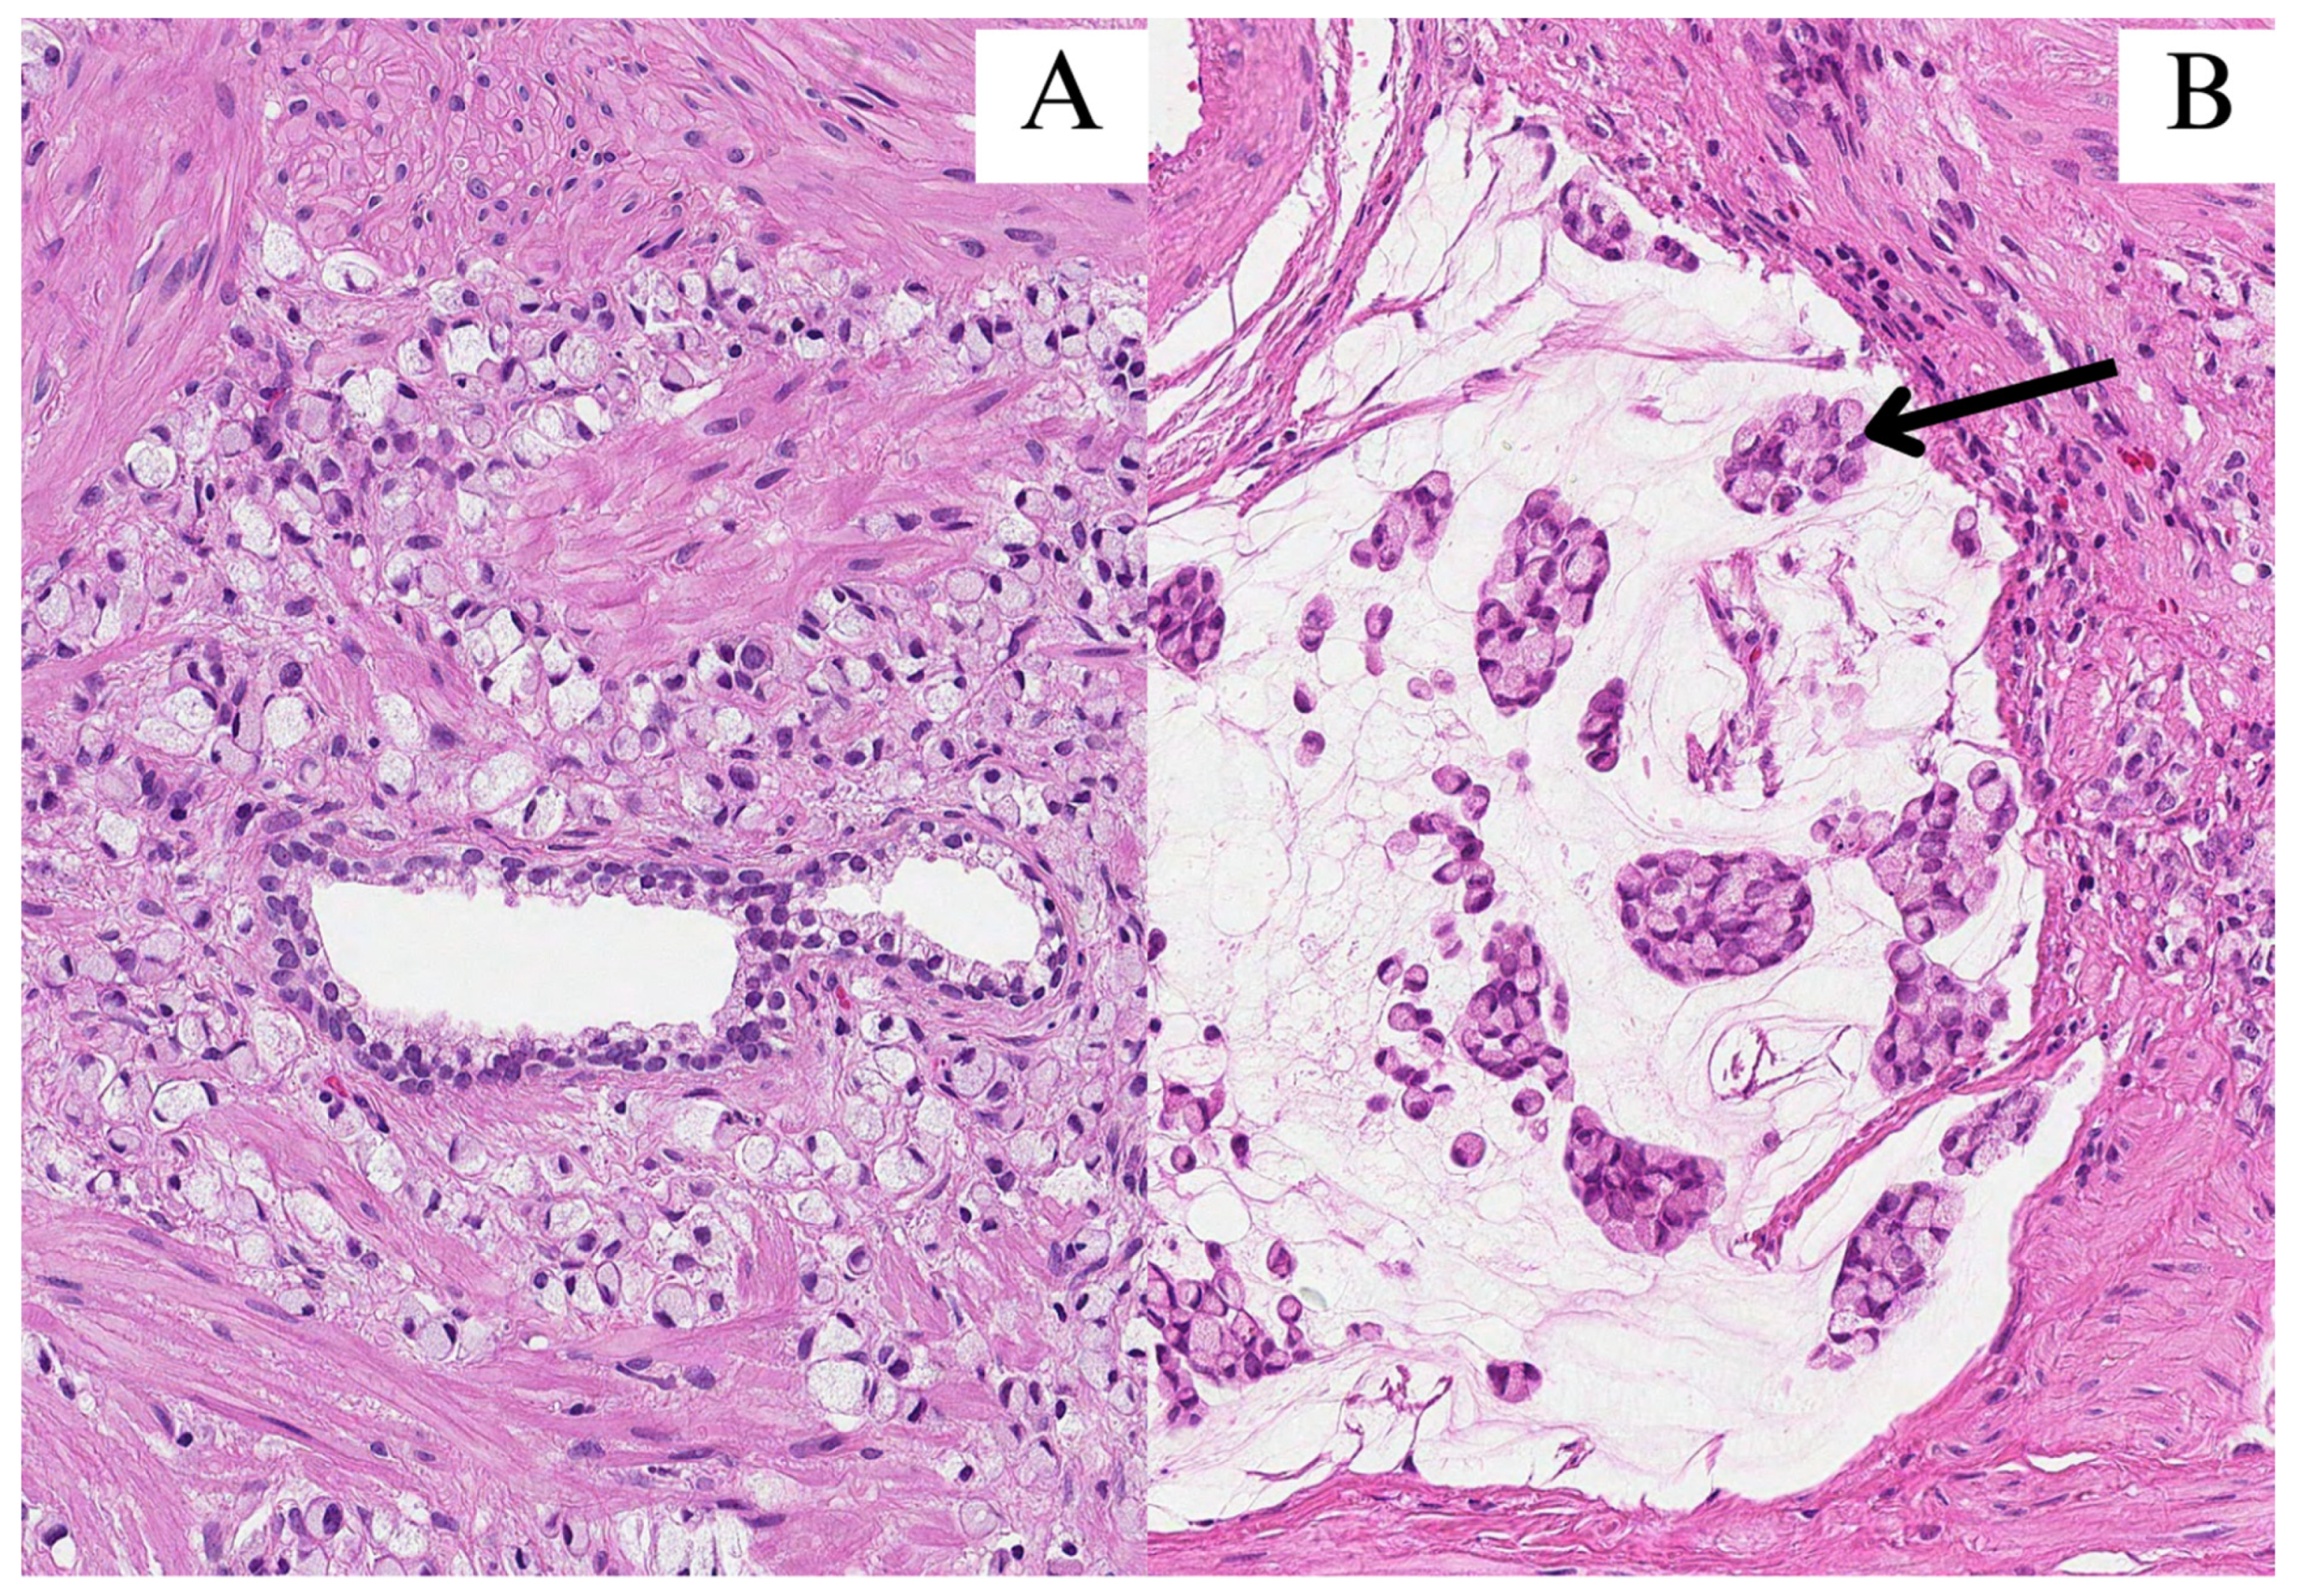

In June of 2023, a 54-year-old Caucasian male with an unremarkable medical history presented with symptoms of episodic hematuria, severe non-specific body aches, shortness of breath, and anuria, which was initially treated with cystostomy before undergoing transurethral prostate resection (TURP). Histopathological examination of the resection revealed a mass of poorly differentiated (G3) adenocarcinoma of an unknown primary site with a diffuse distribution of signet-ring cells (40%) with intracellular and extracellular mucin that constituted 20% of the tumor found within the specimen (Figure 1). An immunophenotype was later determined, and the tumor cells were found to be positive for CDX2; cadherin 17; MUC2; focally for cytokeratin 20 (CK20) and synaptophysin; and negative for CK7, NKX3.1, GATA3, SATB2, MUC5, and MUC6 (Figure 2). Both the visual representation and immunophenotype were suggestive of a metastatic tumor of the lower gastrointestinal tract. Thus, further investigation to verify the primary site was necessary. In search of a primary site, fibrogastroduodenoscopy, chest and abdominal computed tomography (CT), and lesser pelvic magnetic nuclear resonance (MRI) scans were performed, subsequently disclosing erosive gastroduodenopathy, pulmonary embolism (PE), direct seminal vesicle and urinary bladder infiltration, and multiple osteosclerotic metastases—which led to the conclusion that the primary site of SRCC was the prostate gland itself. A TNM class and stage were assigned accordingly—cT4N1M1c stage IV. The patient, with such an advanced disease, did not meet the criteria for radical prostatectomy (RP) or radiation therapy (RT). He was denied chemotherapy due to third-degree thrombocytopenia, due to which antithrombotic treatment, which first was prescribed for PE treatment, was discontinued as well. Infusions of zoledronic acid were initiated. The patient died of cardiopulmonary insufficiency later that week—27 days after the diagnosis was made.

Figure 1.

All images were stained with hematoxylin and eosin (HE) and 200× magnification. (A) Signet-ring cells infiltrated in between prostate glands; (B) clusters of signet-ring cells (arrow) in pools of extracellular mucin.